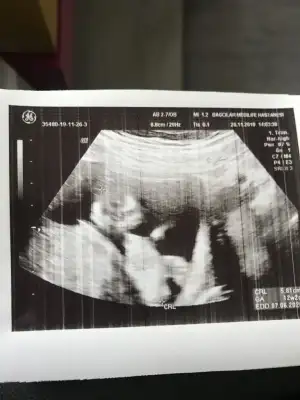

dr soylemeden siz gorun genital nub teorisi ( bebegin cinsiyeti)

Bana da bakar mısınız 🙂